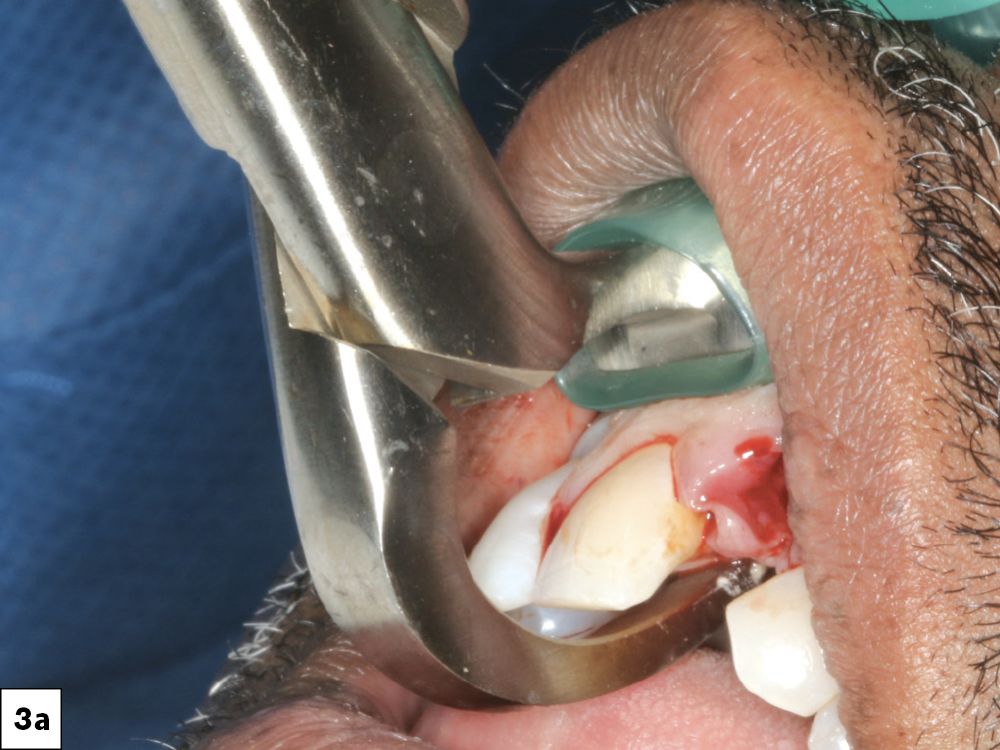

Figures 3a–3c: I extracted the hopeless and compromised teeth, with minimal trauma in order to maintain the facial plate.